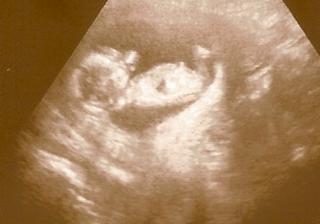

Milé holky, tak to máme za sebou! Miminko bylo velice čilé, mávalo ručičkama, kopalo nožičkama, šudlalo si ručičkama hlavičku (hlavně nosánek, když mu ho paní doktorka chtěla zkontrolovat), různě poskakovalo... Ale paní doktorka ho velice chválila, jak s ní krásně spolupracuje🙂

Šíjové projasnění i nosní kůstky jsou v pořádku. A taky všechno ostatní, co paní doktorka prohlížela.

Miminko je pěkný macík. Nejdřív mělo 6,1 cm, což vyšlo na 13tt + 5, pokud se nemílím. Druhé měření (to už nebylo tak našponované) vyšlo na 5,9 cm. Každopádně je docela napřed... Paní doktorka to přičítá prodloužené kultivaci při IVF a mojí výšce🙂 Krevní testy jsou taky v pořádku. O něco vyšší byla hodnota beta HCG, ale nic alarmujícího. Celkové riziko (i se zohledněním mého věku) na Downův syndrom mám 1:3280, u trizomie 18 téměř 8 tisíc, u trizomie 13 téměř 25 tisíc.

Tákže....včera jsem se dozvěděla pěkný houbelec. Nejdůležitější zpráva, že jsem viděla stále tlouci srdíčko a to mě krásně uklidnilo. Miminko tam ale bylo stočený do tak příšerný polohy, že se nedalo ani změřit, ani vyfotit. Vím pěkný prdlajs, ale doktorka se smála, že vypadá dobře a že budeme mít doma nejspíš atleta. ( minule taky stálo na hlavě ) holky, já se picnu, proč si tam normálně pohodlně nelehne? Takže další kontrola za měsíc, a ve 20.týdnu ultrazvuk v Gennetu.